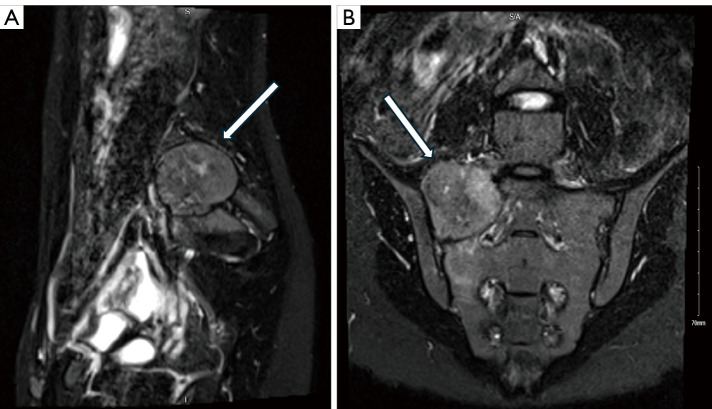

Case description: A 23-year-old female known case of ovarian cyst presented with a two-year history of low back pain and constitutional symptoms. Pelvic magnetic resonance imaging (MRI) with contrast showed a well-defined lesion with intermediate to high signals located at the right wing of the upper sacrum, at the level of S1-S2. The patient underwent a combined ultrasound and computed tomography-guided biopsy under local anesthesia and the immunochemical profile was positive for CD99 and S100 biomarkers. The patient underwent a two-stage procedure for a wide marginal tumor resection. Stage 1 was performed with an anterior approach; identification of the tumor margins was done followed by designing the cuts of the sacrum to achieve wide margins around the tumor. Stage 2 was performed with a posterior approach exposing L3 vertebrae down to the sacrum. Utilizing O-Arm Navigation for posterior margin allocation in addition to instrumentation. After 12 months post-operation, follow up revealed no evidence of recurrence.